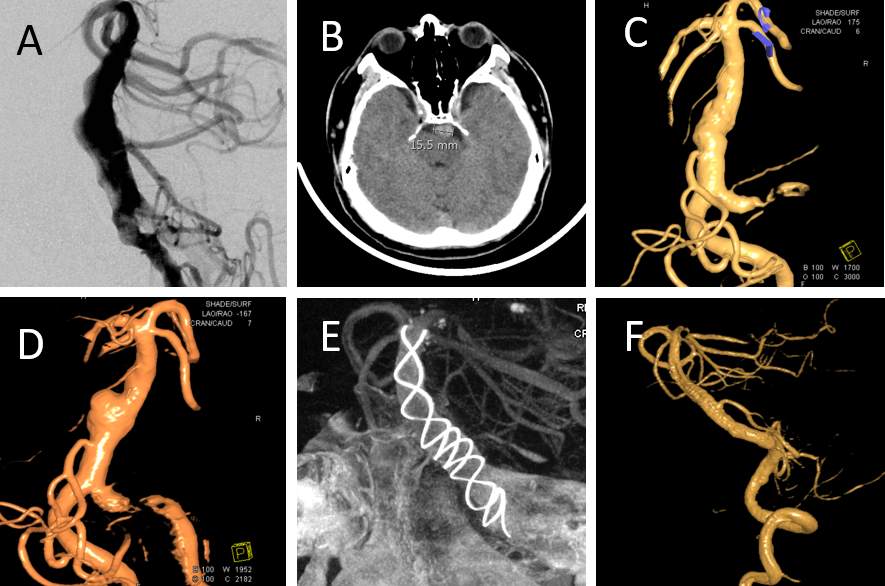

青年男性,35岁,近1个月来出现头痛头晕、流涎、味觉渐渐消失、饮水呛咳、讲话缓慢含糊不清、右侧肢体无力、右侧躯干、肢体及面枕部麻木等症状,并呈进行性加重。在当地医院行颅脑CTA检查,结果发现颅内脑干前方有一个又长又粗的迂曲血管,并向上向前蔓延,像一条匍匐的大“黑龙”(图1A,非真实大小,外面还布满血栓),头颅CT测量最宽处直径15.5mm(图1B,正常2-3mm),诊断:椎基底动脉冗长扩张症。此病是一种罕见的疑难杂症,病因未明,可能与局部血管结构先天或者后天的薄弱所致。此处血管布满许多脑干穿支和分支血管,周围毗邻众多的颅神经、脑干(内含重要的传导束、神经核团等)、小脑、三脑室及其下行的脑脊液管道系统等重要结构。当此处的血管迂曲变长变粗之后,就会压迫上述的正常结构出现相应症状,诸如,脑梗塞、出血、占位效应(诸如三叉神经痛)和脑积水等症状。患者一旦出现症状,进展大多迅速,死亡率和致残率极高,本病为最复杂、最棘手和最有挑战性的脑血管病之一,文献大多集中在流行病学和影像学方面。目前,国际上没有成熟的可以推荐的治疗方法可以借鉴,治疗的不确定性让人望而生畏。

图1.椎基底动脉冗长扩张症的治疗过程

手术当日,造影发现患者的血管形态已经在短时间内明显发生改变,局部血管继续增粗扩张,并呈现明显的瘤样突起(图1C-1D),一期闭塞血管显然已经不是最佳选择。基于我们术中充分的影像学评估,决定为患者进行血流导向装置(Tubridge)植入术。血流导向装置又称为密网支架,是一种新型的介入材料,是神经介入材料的一次革新,改变了囊状大型动脉瘤的治疗史。由于其支架的网眼非常小,导丝非常细,会干扰并减少从载瘤动脉进入动脉瘤的血流,表现为“血流导向”作用,导致动脉瘤内血栓形成,主要用于前循环颅内大型囊状动脉瘤的治疗。但是,在含有众多穿支和分支血管的椎基底动脉上植入国产新型血流导向装置是一个全新的尝试,手术需要同时达到以下目的:支架的周围慢慢形成血栓、基底动脉的众多穿支和分支血管通畅、瘤样突起消失、对侧椎动脉冲击血管的地方血流减少,这对术者和围手术期管理都提出了极高的挑战,让人望而却步。再次和患者家属进行充分沟通后,全麻下顺利完成手术,导管安全到位,规格合适的Tubridge打开充分并良好贴壁,瘤样扩张的地方和右侧椎动脉汇合冲击的地方进行了专门调控加固,局部拥有了更高的金属覆盖率。术后,上述目的全部达到(图1E):血管得到重建、穿支/分支保留、瘤样扩张得到控制、支架局部的高金属覆盖率让来自右侧椎动脉的冲击血流减少。

术后,患者精神状态明显改善,症状持续进行性缓解或消失:头痛头晕消失、右侧躯干肢体及面枕部麻木基本消失、消失的味觉重新恢复、饮水呛咳和流涎明显缓解、共济失调明显改善、讲话清晰、右侧肢体肌力恢复正常。术后10天再次DSA复查:扩张的血管已经恢复正常(图1F)。目前,患者及家人已乘飞机安全返回家乡,很快就会重返工作岗位。